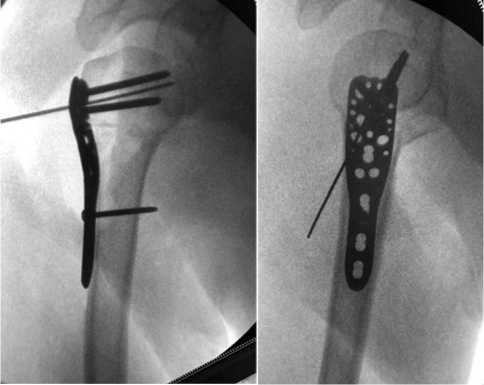

После завершения репозиции отломков приступали к фиксации пластины блокируемыми винтами. Удерживая нити в натянутом состоянии и плотно прижимая пластину к кости, последовательно рассверливали отверстия в наиболее удобно расположенных точках пластины, начиная с верхнепереднего квадрата. Выбор именно этих отверстий для первичной фиксации определен их хорошей доступностью через операционный доступ и возможностью надежно закрепить проксимальный фрагмент. После установки проксимальных винтов переходили к фиксации дистальной части пластины, для чего через овальное отверстие вкручивали кортикальный винт диаметром 3,5 мм, тщательно следя за тем, чтобы передний край пластины располагался позади сухожилия длинной головки двуглавой мышцы плеча. На протяжении всего процесса фиксации осуществляли постоянный контроль положения отломков и имплантата с помощью ЭОП, при необходимости корректируя положение винтов. Особое внимание уделяли равномерному распределению усилий при затягивании винтов, чтобы избежать перекоса пластины и обеспечить ее плотное прилегание по всей поверхности кости. После завершения фиксации проводили оценку стабильности конструкции и качества репозиции (рис. 4).

На завершающем этапе операции выполняли последовательное затягивание и фиксацию нитей

Рис. 4. Рентгенологическая оценка репозиции перелома на пластине

к пластине с последующим удалением временной центральной спицы Киршнера и установкой дополнительных блокируемых винтов. Особое внимание уделяли подбору длины проксимальных винтов, — при переломах типа C по классификации

AO–ASIF предпочтение отдавали укороченным винтам, что связано с риском развития частичного ава-скулярного некроза головки плечевой кости и необходимостью минимизировать риск прорезывания костной ткани. Ключевыми аспектами успешной репозиции являлись: восстановление анатомического объема головки плечевой кости за счет применения костной пластики и обязательная фиксация сухожилий вращательной манжеты плеча к пластине. Отдельно следует отметить технический нюанс, связанный с первоначальной фиксацией диафиза, — из-за чрезмерной длины репозиционного кортикального винта осуществляли его последующую замену на более короткие винты (рис. 5). Данный подход позволял оптимизировать распределение нагрузки и снижать риск развития осложнений, связанных с избыточной длиной фиксирующих элементов.

Рис. 5. Фото и рентгенограммы при окончательной фиксации перелома